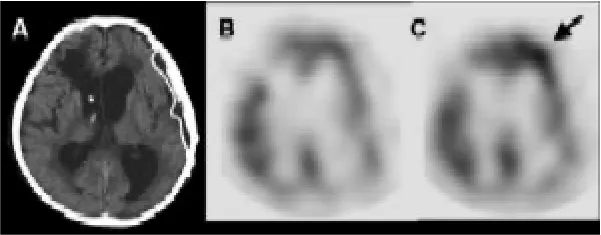

遷延性意識障害に近赤外線治療を行った

症例の提示低出力近赤外線照射誘発機能的fMRI検査で、前頭葉機能の評価と、前頭葉賦活法を行います。基本的に保険診療の頭部MRIの適応の範囲内で行う検査です。高磁場MRI室に設置した810nm CW diode laser装置をもとにして、非磁性体で作成した7mの光ファイバーを通して、被験者の前額部に近赤外線を照射し、照射前、照射中の信号変化を測定しfMRIを撮像します(下図)。近赤外線は温熱効果が少なく、米国FDAとANSIで定められた安全基準の320mW/cm2より、はるかに少ないエネルギー密度で照射し、皮膚の熱感も起こさないレベルです。

Nawashiro H, Wada K, Nakai K, and Sato S: Photomed. Laser. Surg. 30 (2012) 231. -

【症例】40歳男性 交通外傷で、受傷。 昏睡状態で搬送され、急性硬膜下血腫、脳挫傷と診断された。開頭血腫除去・外減圧術で救命した。 しかし、8ヶ月以上、四肢自動運動無く、開眼するも追視なく、従命が全く取れない状態が持続した。 ご家族の同意を得て、前額部にLED(出力:13mW x 23 = 299mW)による近赤外光治療を朝夕30分間2回、73日間施行した。 治療後、照射部位の頭皮にトラブルは無く、左上肢の自動運動、合目的運動が出現し、前頭葉脳血流の有意な増加を認めた。